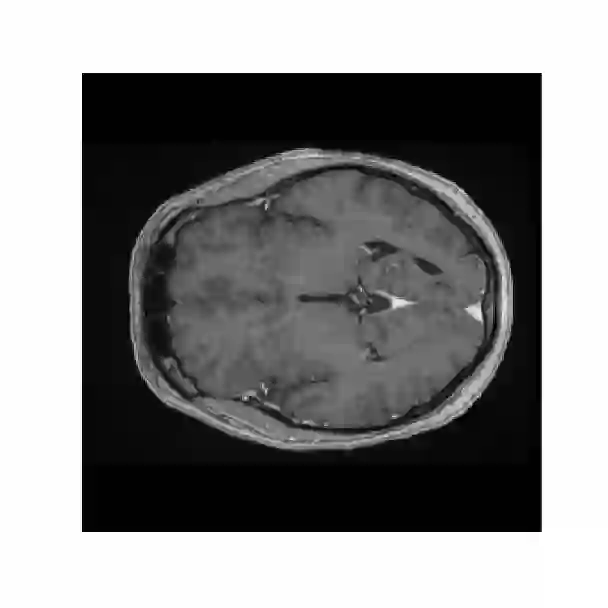

Objectives: Present a novel deep learning-based skull stripping algorithm for magnetic resonance imaging (MRI) that works directly in the information rich k-space. Materials and Methods: Using two datasets from different institutions with a total of 36,900 MRI slices, we trained a deep learning-based model to work directly with the complex raw k-space data. Skull stripping performed by HD-BET (Brain Extraction Tool) in the image domain were used as the ground truth. Results: Both datasets were very similar to the ground truth (DICE scores of 92\%-98\% and Hausdorff distances of under 5.5 mm). Results on slices above the eye-region reach DICE scores of up to 99\%, while the accuracy drops in regions around the eyes and below, with partially blurred output. The output of k-strip often smoothed edges at the demarcation to the skull. Binary masks are created with an appropriate threshold. Conclusion: With this proof-of-concept study, we were able to show the feasibility of working in the k-space frequency domain, preserving phase information, with consistent results. Future research should be dedicated to discovering additional ways the k-space can be used for innovative image analysis and further workflows.

翻译:提出磁共振成像(MRI)基于深层次学习的磁共振成像头骨剥离算法(MRI),该算法在信息丰富k-空间中直接发挥作用。材料和方法:利用来自不同机构的两套数据集,总共36 900 MRI片,我们训练了一个深层次学习模型,直接与复杂的原始K-空间数据合作。由HD-BET(Brain提取工具)在图像领域进行的Skull剥离过程被用作地面真相。结果:两个数据集都与地面真相非常相似(DICE分数92 ⁇ -98 ⁇ 和Hausdorff在5.5毫米以下的距离)。眼睛区域上的切片达到99 ⁇ 的DICE分数,而精度则在眼睛和下面区域下降,结果部分模糊。Kstrip的输出往往在头骨的标界边缘平滑。用一个适当的阈值创建了Binary面具。结论:通过这一检验研究,我们得以显示在K-空间频域内工作的可行性,保存阶段信息,并使用进一步探索K-空间图像的方法。